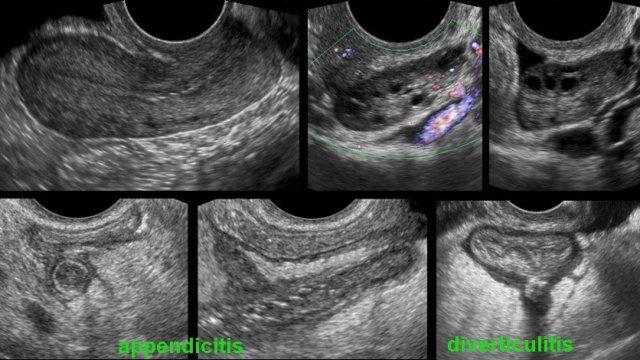

Nó cũng có thể được sử dụng cho các tình trạng không phải phụ khoa như viêm ruột thừa, viêm túi thừa, v.v.

Việc sử dụng siêu âm qua âm đạo sẽ được đề cập trong một bài viết khác: Siêu âm qua âm đạo cho các bệnh lý không thuộc phụ khoa.